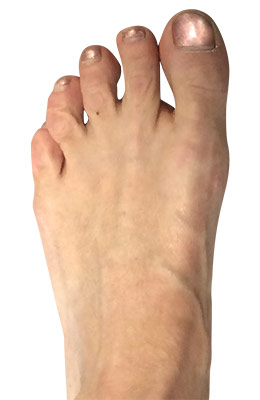

Before

Minimally Invasive Bunion Surgery before

After

Minimally Invasive Bunion Surgery after

Minimally Invasive Bunion Surgery featuring the miniBunon™ System and Tailors Bunionectomy

Melissa is a 32-year-old businesswoman who could not be off her foot post-surgery, yet she had a severely painful bunion. We performed our miniBunon™ System (our trademarked minimally invasive bunion surgery) and had a dramatic correction with no downtime. Melissa continued to work after her bunion surgery and was back in shoes and full activity at 5 weeks. Melissa could not believe the results of her Bunionectomy resulting in no bony bump, no scar and amazing motion. “After” picture taken immediately following surgery. Note the bunion and bunionette (Tailor’s bunion) in the before picture.